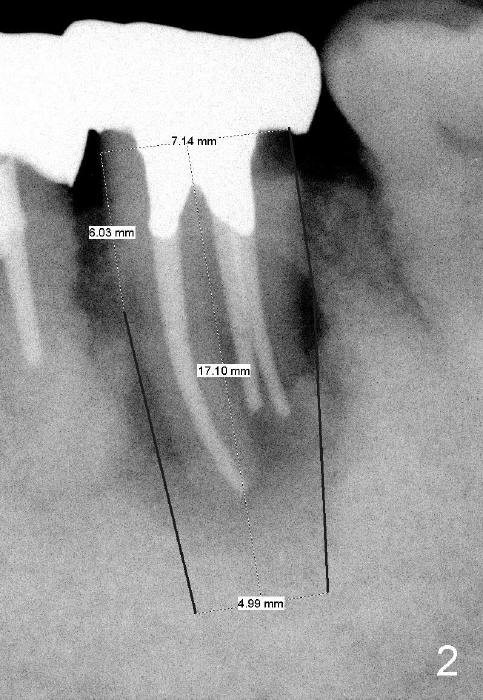

The initial trajectory using 2 mm pilot drill is off (Fig.4), whereas the 2nd one is good (Fig.5).